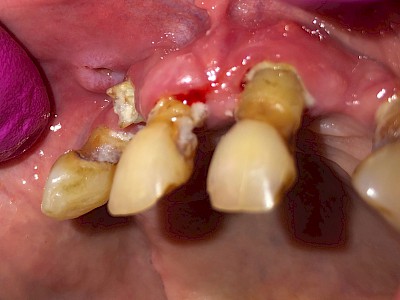

Krone: Randspalt

Randspalten bzw. Defekte im Randbereich sind immer auch verdächtig für Karies.